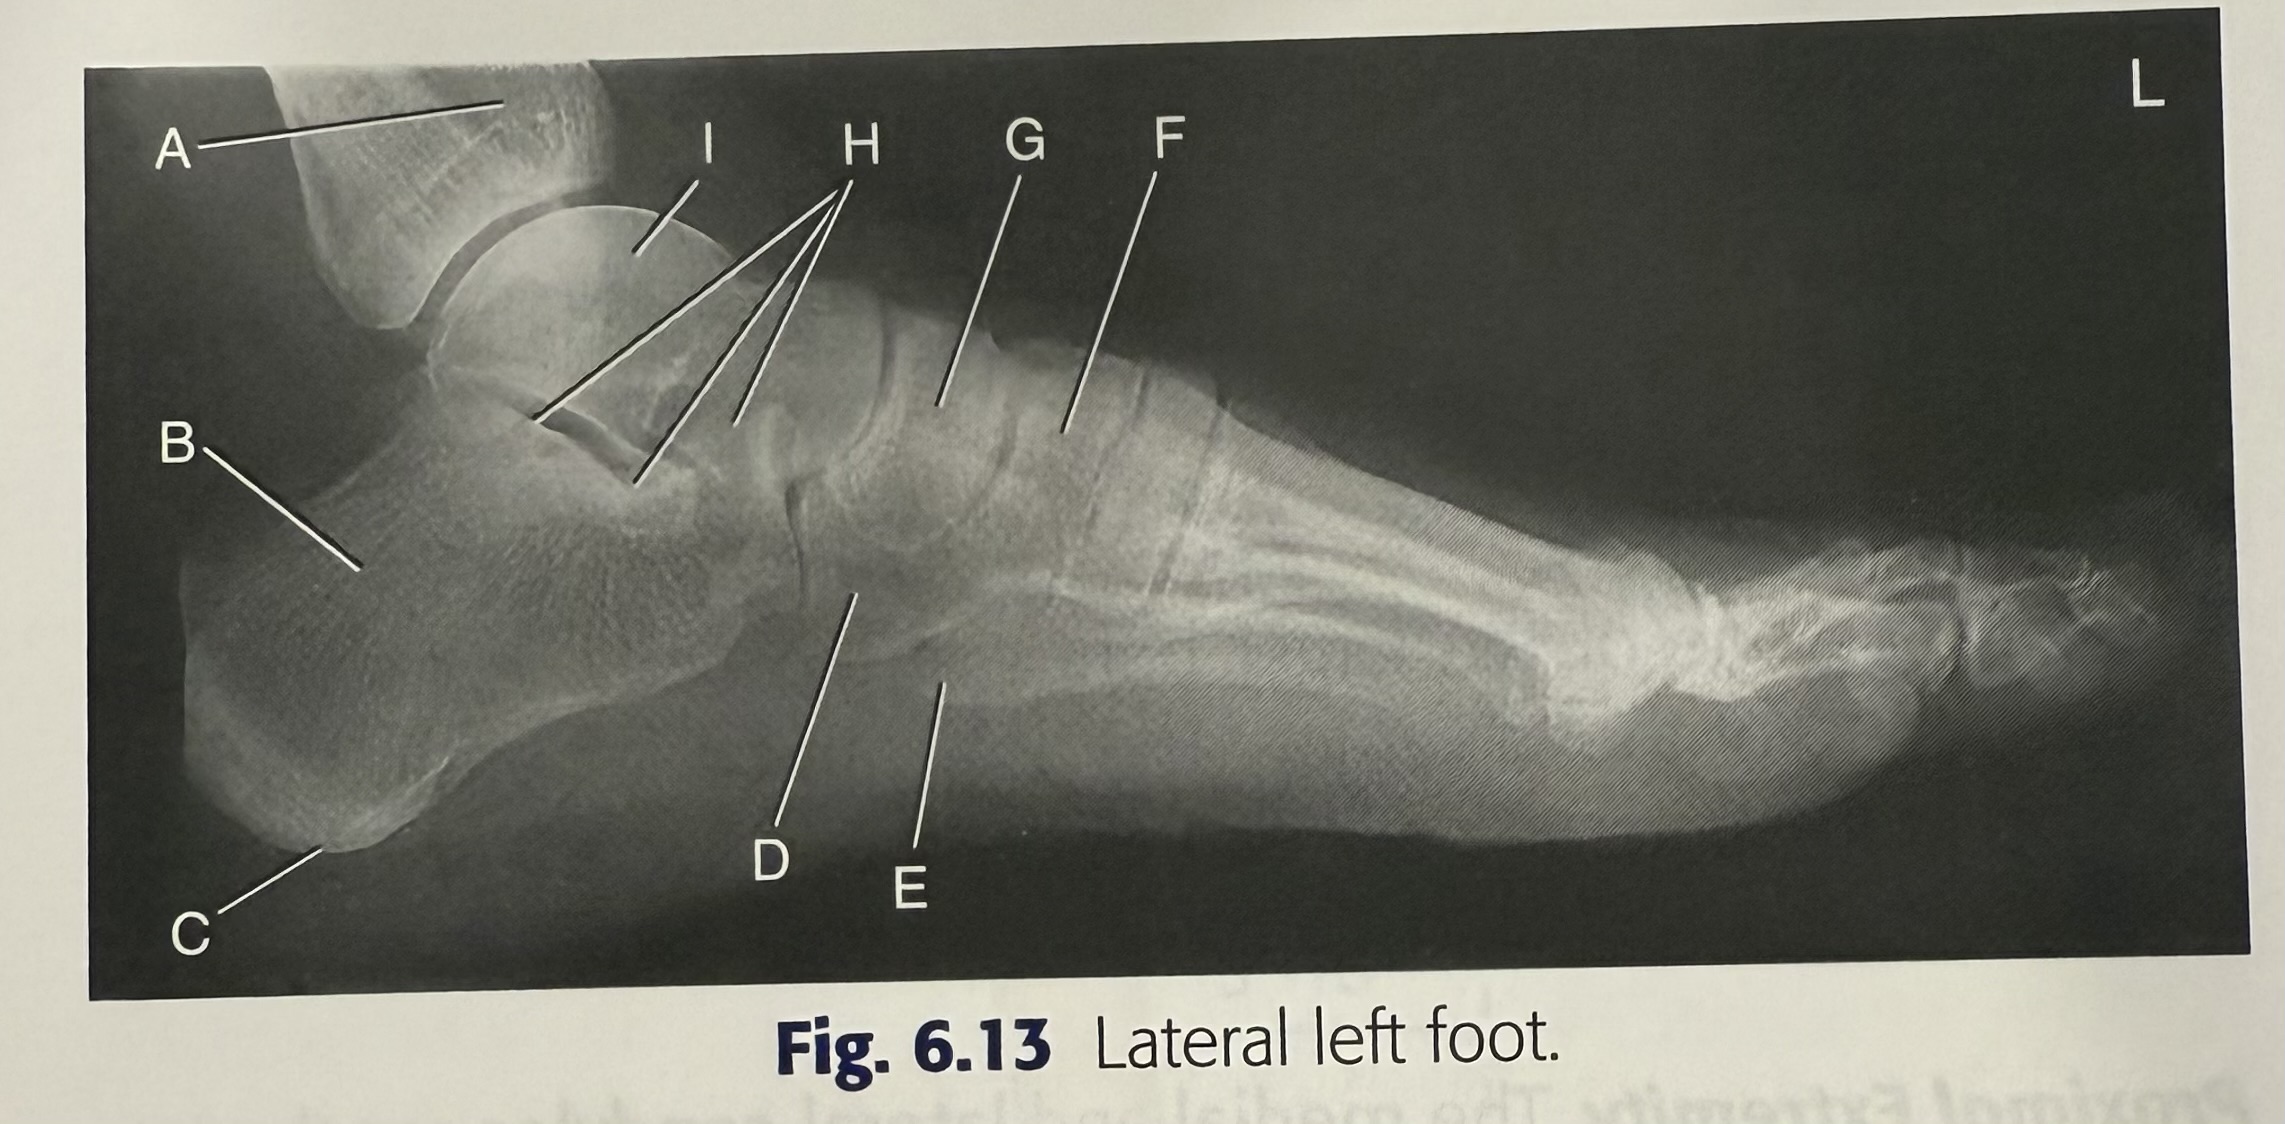

<p>A</p>

tibia

<p>B</p>

calcaneus

<p>C</p>

tuberosity of calcaneus

<p>D</p>

cuboid

<p>E</p>

5th metatarsal tuberosity

<p>F</p>

superimposed cuneiforms

<p>G</p>

navicular

<p>H</p>

subtalar joint

93

<p>I</p>

talus